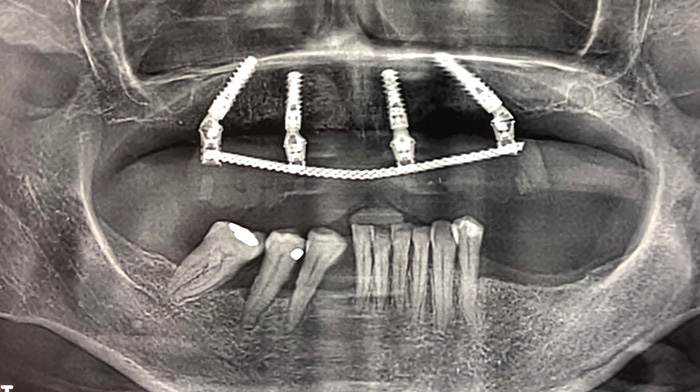

Fig. 19 : Panoramique de contrôle après lequel le vissage au niveau de l’implant en 25 sera repris.

Fig. 2 : Indication de la pose de 4 implants maxillaires selon les zones de E. Bedrossian (Bedrossian E et al. Fixed-prosthetic Implant Restoration of the Edentulous Maxilla: A Systematic Pretreatment Evaluation Method. J Oral Maxillofac Surg 2008;66:112-22 ) et suivant le protocole de P. Malo (All-on-4 immediate-function concept with Brånemark System implants for completely edentulous maxillae: a 1-year retrospective clinical study.

Maló P, Rangert B, Nobre M.).

Fig. 7 : Objectivation des axes implantaires après pose de 4 nouveaux piliers coniques SRA (2 droits en hauteur 2.5 et 2 angulés à 30° pour les implants postérieurs).